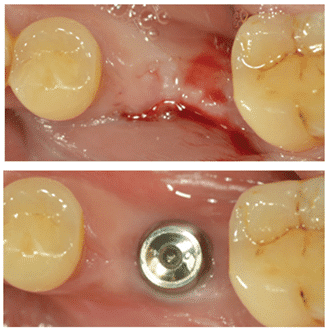

(Figure 3) Placement du MagiCore dans un os de faible largeur.

Contrairement aux implants bone level, en deux parties, il n’est pas difficile de rencontrer ces conditions avec le système d’implant MagiCore (figure 3).

Un autre avantage du Magic Cuff est qu’il ne compromet pas l’étanchéité des tissus péri-implantaires cicatrisés autour de l’implant, même après une longue période post-opératoire, ce qui permet d’obtenir des tissus péri-implantaires esthétiques.

En général, l’étanchéité des tissus péri-implantaires autour d’un implant bone level en deux parties peut être endommagée lors de la prise d’empreinte et du processus de pose de la couronne. Cependant, MagiCore préserve la santé des tissus péri-implantaires en utilisant le Magic Cuff, dont le traitement de surface et la conception favorisent l’adhésion des tissus.